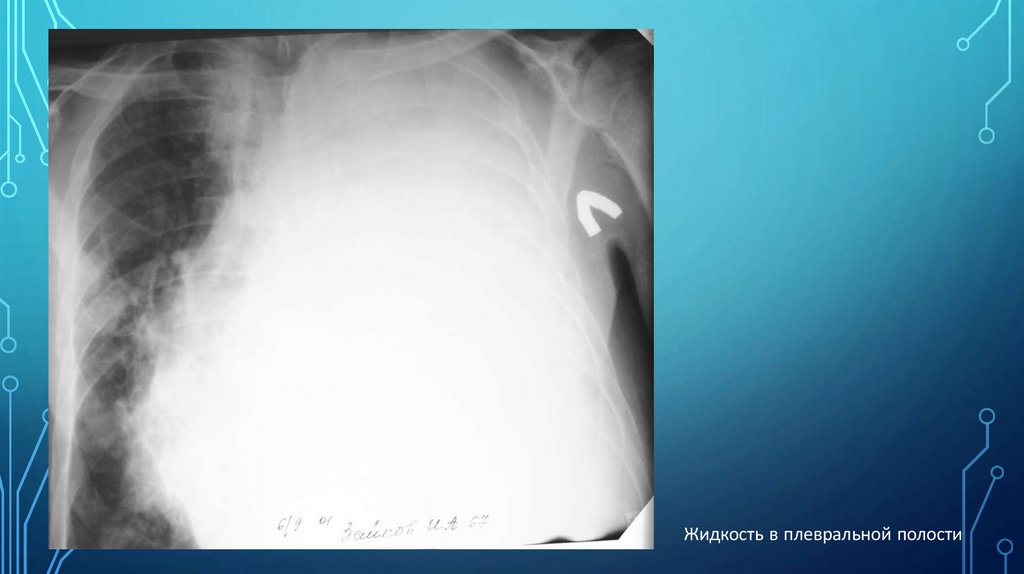

Жидкость в плевральной полости

А)Свободная жидкость в плевральной полости в прямой проекции при

вертикальном положении больного проявляется однородным затененим нижне-латеральной

части легочного поля с косой верхней границей (линия Эллиса-Дамуазо), контур ее нечеткий,

при вдохе смещается вниз, при выдохе – вверх